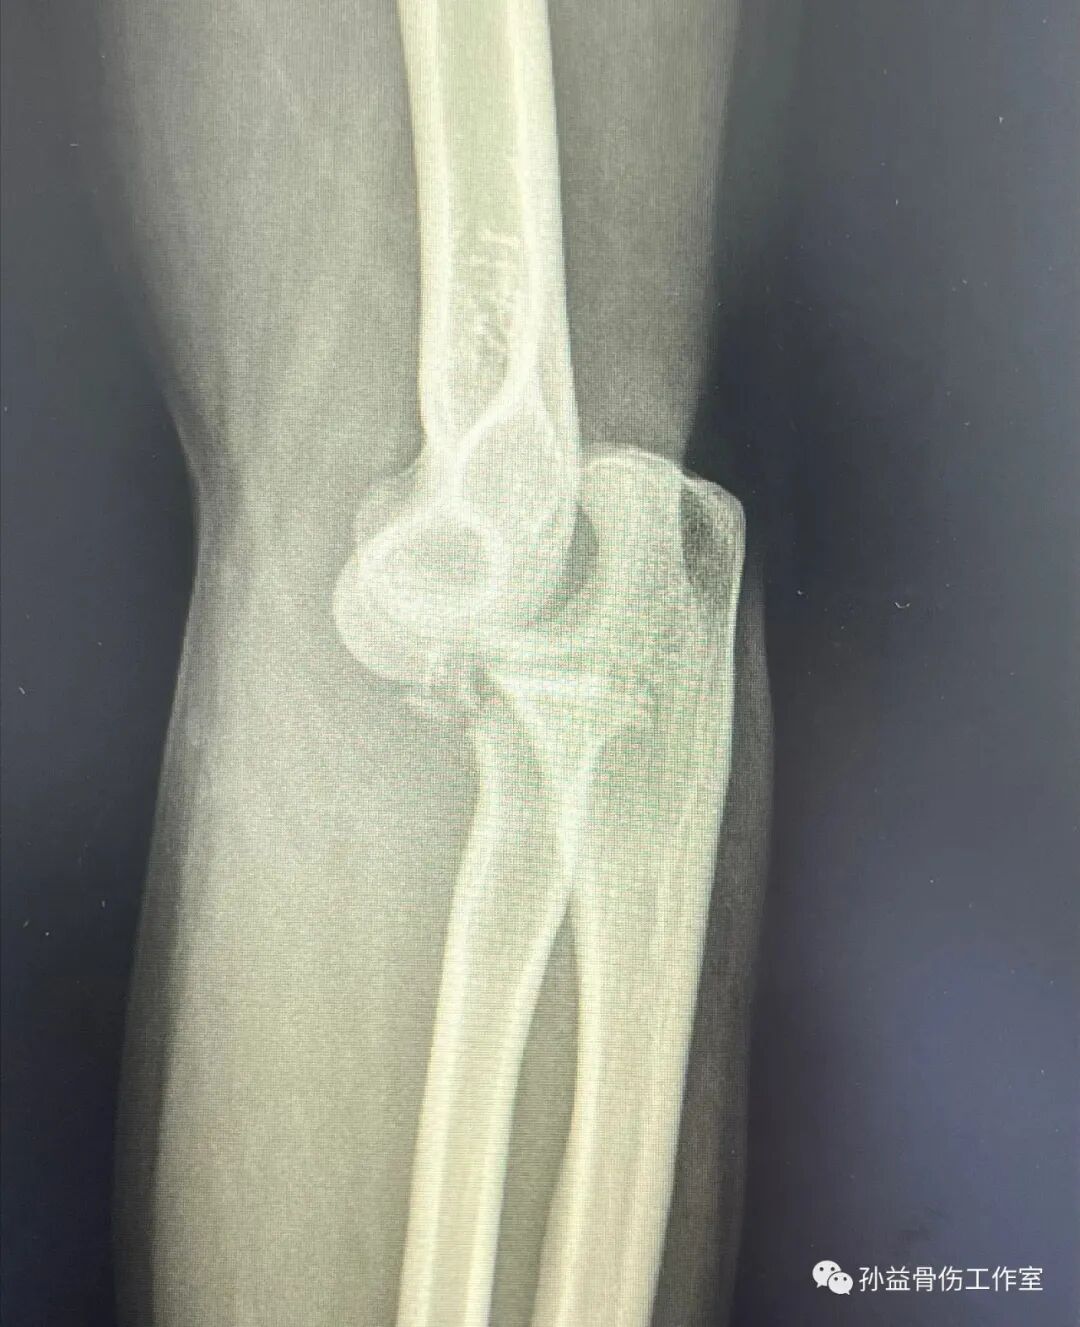

小宋是個運動愛好者,喜歡各種劇烈的體育運動,幾個月前在運動過程中不慎跌倒,左肘部直接著地,當時明顯可以感覺到整個手肘都變了形,周圍的伙伴看到扭曲的手肘驚出一身冷汗,急忙將他送到附近的醫院進行治療。

到了急診進行檢查后發現小宋的肘關節處在一個后脫位的狀態,橈骨小頭,尺骨冠狀突等多處部位出現骨折,最后診斷為肘關節的嚴重骨折伴脫位,號稱是肘關節可怕的恐怖三聯征。按照過往的治療經驗,這樣的嚴重的復合性損傷意味著他今后將要面對肘關節的部分殘疾,就是我們常說的要留下后遺癥了。